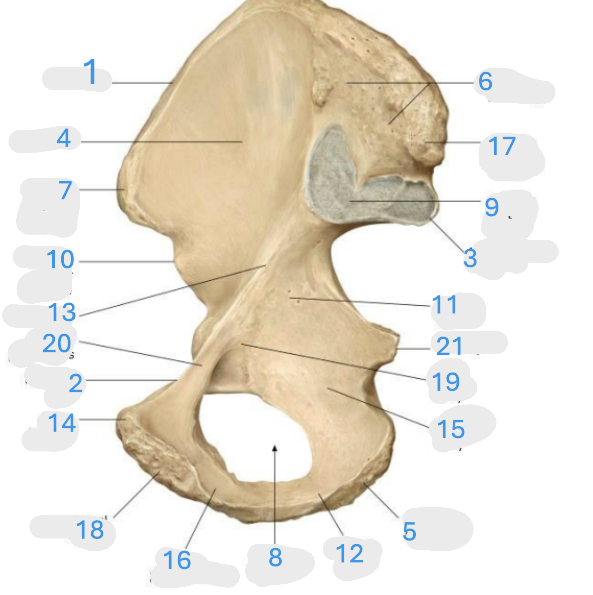

Where is the iliac crest

1

Where is the pectineal line

2

Where is the posterior iliac spine

3

Where is the iliac fossa

4

Where is the ischial tuberosity

5

Where is the iliac tuberosity

6

Where is the anterior superior iliac spine

7

Where is the obturator foramen

8

Where is the auricular surface of the ilium

9

Where is the anterior inferior iliac spine

10

Where is the ilium body

11

Where is the ischial ramus

12

Where is the arcuate line

13

Where is the pubic tubercle

14

Where is the ischium body

15

Where is the inferior pubic ramus

16

Posterior superior iliac spine

17

Where is the symphyseal surface

18

Where is the pubis body

19

Where is the superior pubic ramus

20

Where is the ischium body

21